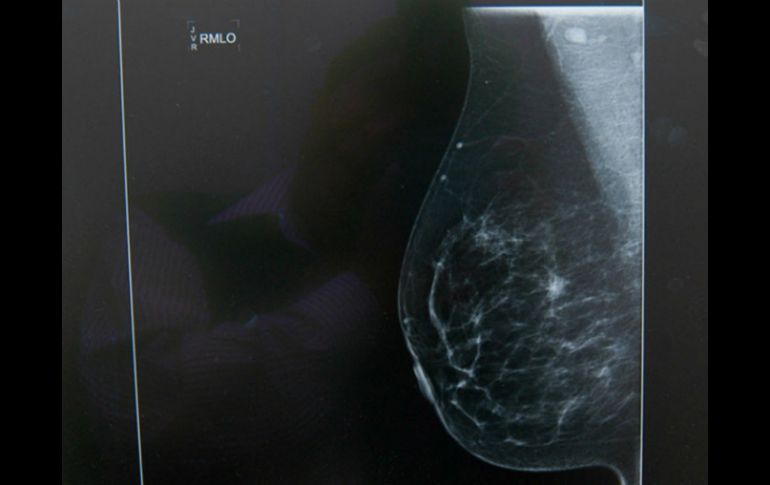

Tecnología | El objetivo es lograr segmentar distintos tipos y detalles de estructuras de interés Analizan nuevas técnicas para mejorar resultados de imágenes médicas El objetivo es lograr segmentar distintos tipos y detalles de estructuras de interés Por: NTX 6 de enero de 2016 - 16:17 hs Los autores esperan que en trabajos futuros los nuevos métodos se segmentación ayuden a la localización de tumores. EL INFORMADOR / ARCHIVO CIUDAD DE MÉXICO (06/ENE/2016).- La Universidad Autónoma de San Luis Potosí (UASLP) estudia diversas técnicas para mejorar el análisis de imágenes médicas, pues la imagenología clínica permite explorar a detalle las principales funciones del cuerpo. La alumna de la Facultad de Ciencias, Sarahí Hernández Juárez, trabaja para realizar comparaciones cuantitativas de métodos de segmentación de imágenes médicas, para lograr organizar distintos tipos de estructuras del cuerpo. Este trabajo se realiza bajo la tutoría de los doctores Aldo Mejía y Edgar Arce, en colaboración con el Instituto de Bioimagenología y Fisiología Molecular que se encuentra en Milán, Italia, quienes aportan imágenes de casos clínicos verdaderos. "El objetivo inicial del proyecto era comparar métodos de segmentación en el ámbito clínico para lograr segmentar distintos tipos de estructuras de interés", dijo Hernández en una entrevista con la Agencia Informativa del Consejo Nacional de Ciencia y Tecnología ( Conacyt). "Después se complementó con la comparación por parte de un experto clínico, para verificar la eficiencia de los métodos de segmentación conocidos, en este caso enfocado en el tratamiento de radioterapia", añadió. Los métodos que se aplicaron fueron K-means, Otsu y Chan-Vese para la segmentación de imágenes de pulmones y un tumor cerebral. El análisis cuantitativo constó del cálculo de índices de precisión que comparan la segmentación obtenida por cada método con otra de forma tradicional por un especialista clínico. Los índices adquiridos fueron la distancia simétrica media, la distancia máxima, el porcentaje de distancias mayores a la dimensión del pixel y el índice de superposición. Los resultados arrojaron que para la segmentación de los pulmones los algoritmos se comportan de manera similar, pero en el caso del tumor, el método de Chan-Vese es preferible. "Podemos decir que los métodos de segmentación nos pueden dar mucha información característica de las estructuras, por ejemplo en este caso se evalúo el tumor de un cerebro", dijo la encargada del proyecto. "Así que se puede aplicar en el área de radioterapia y darle un sentido más real", añadió. Los autores esperan en trabajos futuros complementarlo con otros métodos de segmentación de imágenes médicas para aplicaciones en la localización y tratamiento de tumores. Temas Cáncer Investigación científica Ciencia médica Tumor Lee También Estudio chino revela una mutación que eleva riesgo de alzhéimer Esta terapia podría revolucionar el tratamiento oncológico en Latinoamérica ¿Cómo se forman los recuerdos en la mente? Esto dijo Israel sobre la extradición de Zerón a México Recibe las últimas noticias en tu e-mail Todo lo que necesitas saber para comenzar tu día Registrarse implica aceptar los Términos y Condiciones